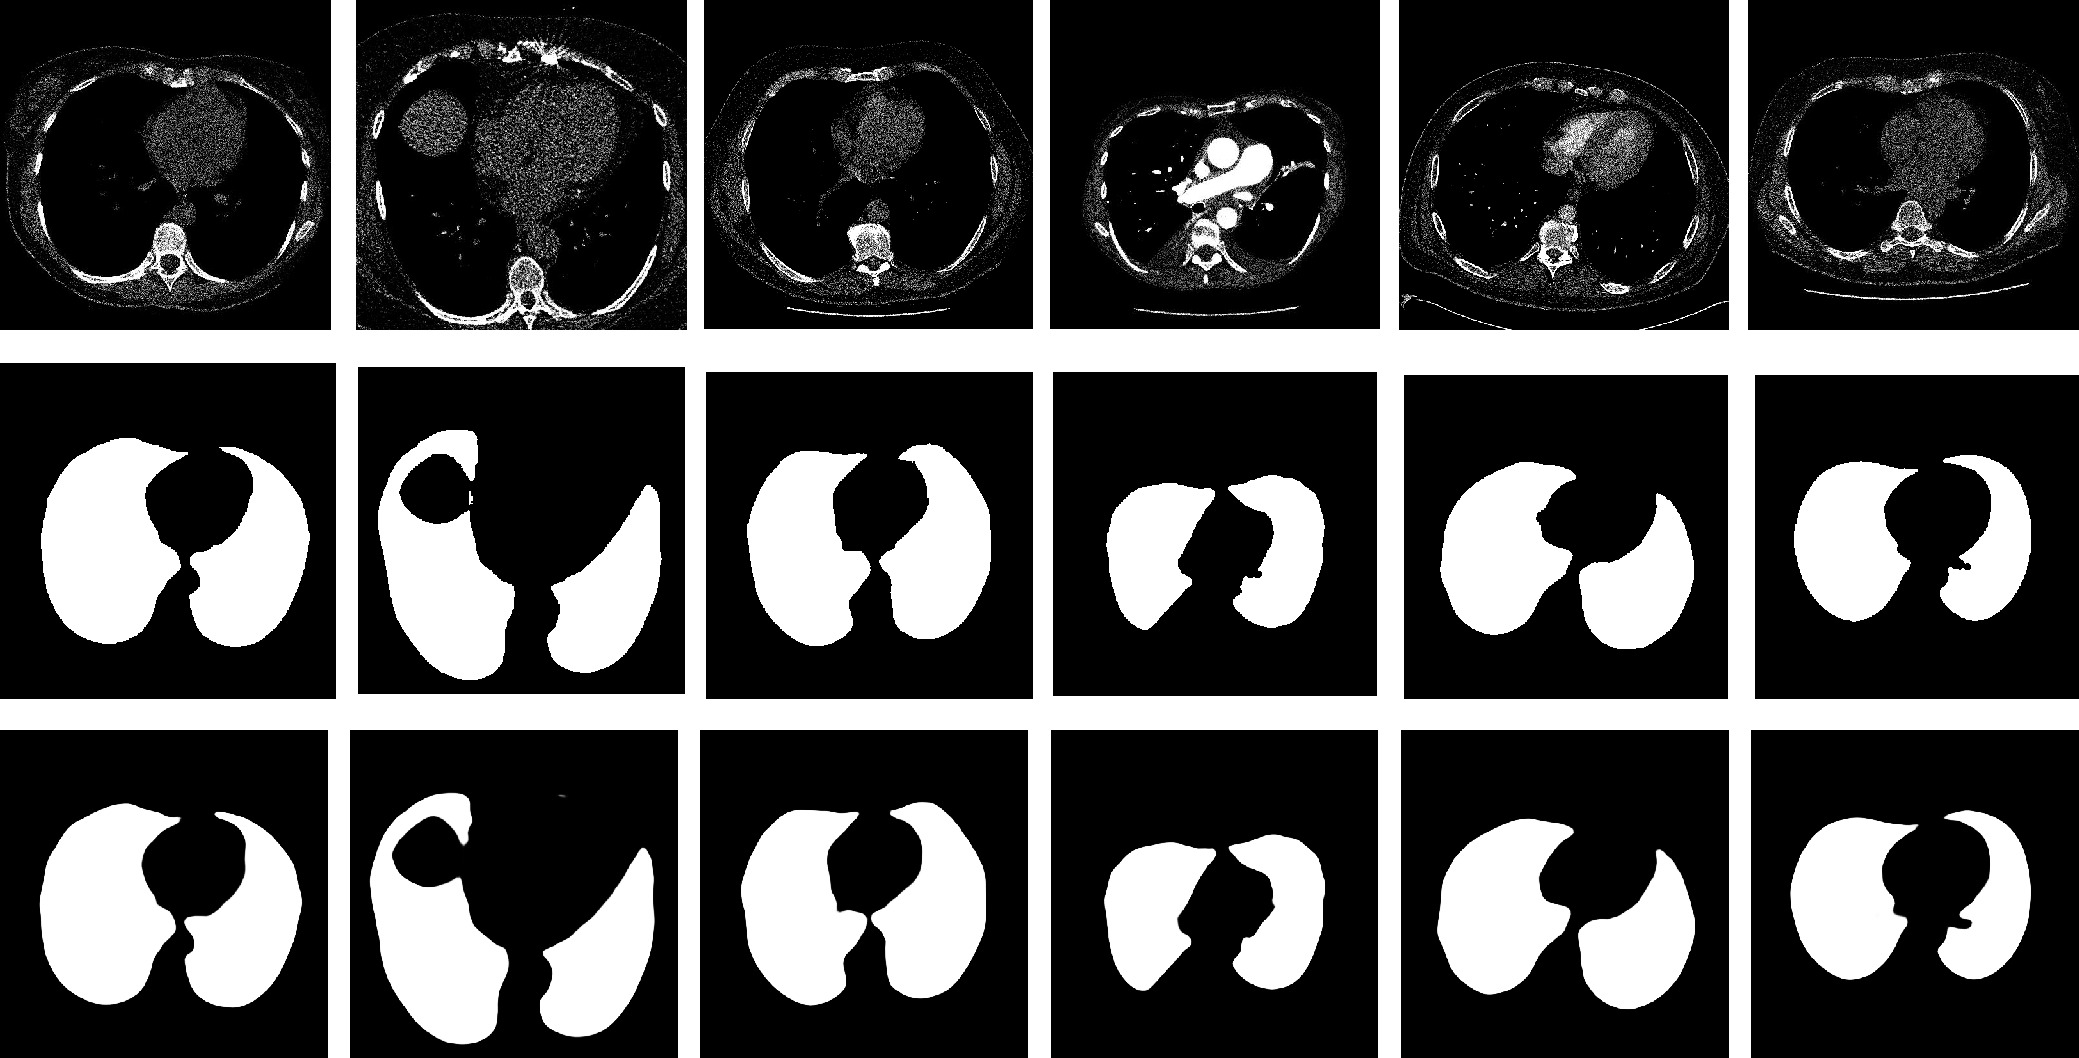

MFAINet: Multi-Receptive Field Feature Fusion With Attention-Integrated for Polyp Segmentation

Guangzu Lv, Bin Wang, Cunlu Xu, Weiping Ding, Jun Liu

2026, 13(4): 822-836. doi: 10.1109/JAS.2025.125408

Abstract(1364) HTML (87) PDF(70)

Abstract:

Colorectal cancer has become a global public health concern. Removing polyps before they become malignant can effectively prevent the onset of colorectal cancer. Currently, multi-receptive field feature extraction and attention mechanisms have achieved significant success in polyp segmentation. However, how to effectively fuse these mechanisms and fully leverage their respective strengths remains an open problem. In this paper, we propose a polyp segmentation network, MFAINet. We design an attention-integrated multi-receptive field feature extraction module (AMFE), which uses layering and multiple weightings to fuse the multi-receptive field feature extraction and attention mechanisms, maximizing the extraction of both global and detailed information from the image. To ensure that the input to AMFE contains richer target feature information, we introduce a multi-layer progressive fusion module (MPF). MPF progressively merges features at each layer, fully integrating contextual information. Finally, we employ the selective fusion module (SFM) to combine the high-level features produced by AMFE, resulting in an accurate polyp segmentation map. To evaluate the learning and generalization capabilities of MFAINet, we conduct experiments on five widely-used public polyp datasets using four evaluation metrics. Notably, our model achieves the best results in nearly all cases.